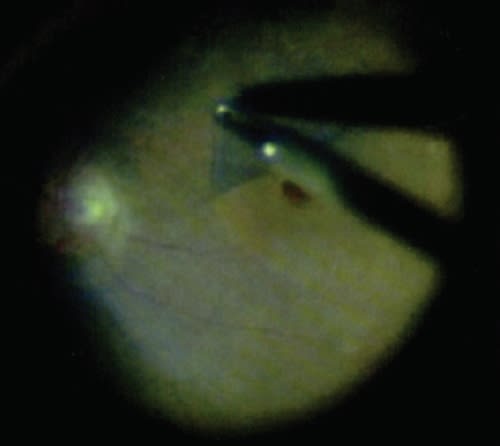

Triamcinolone's use in visualization was discovered largely by accident; its water-insolubility caused it to be retained for longer periods in the vitreous, which would then have augmented visualization in postoperative examinations.6 Since then, triamcinolone has been used in anterior- segment surgery and pars plana vitrectomy to visualize the vitreous and minimize or eliminate loss of vitreous. More recently, it has been applied to the ILM for peeling during macular hole surgery (Figure 2).7,16

Figure 2. Membrane peel after triamcinolone acetonide application.